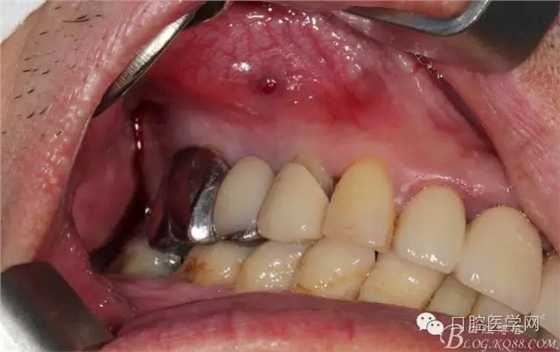

牙周治療以后過了段時間我們開始拔牙種牙,上圖是牙周治療以后開始種牙的口內(nèi)照片,效果還是有的。

簡單清理以后 (一般這種情況我是不太翻瓣的)這個患者我在清理13遠中時候我發(fā)現(xiàn)有些肉芽而且超過了我的預(yù)期的量,我開始不太淡定了 。 我在想牙周科同事是不是知道我要拔牙,沒有在14 16 牙位用洪荒之力刮治啊。結(jié)果我翻瓣一點點去檢驗了下牙周科刮治的效果,那么結(jié)果是非常好,沒啥太多的肉芽,不翻瓣完全可以刮干凈,看來我得信任我的同事啊,牙周科非常給力。13牙位遠中的肉芽估計的確不好刮掉,所以留給我刮了吧。

軟組織簡單處理以后 簡單縫合 植體三維空間非常理想